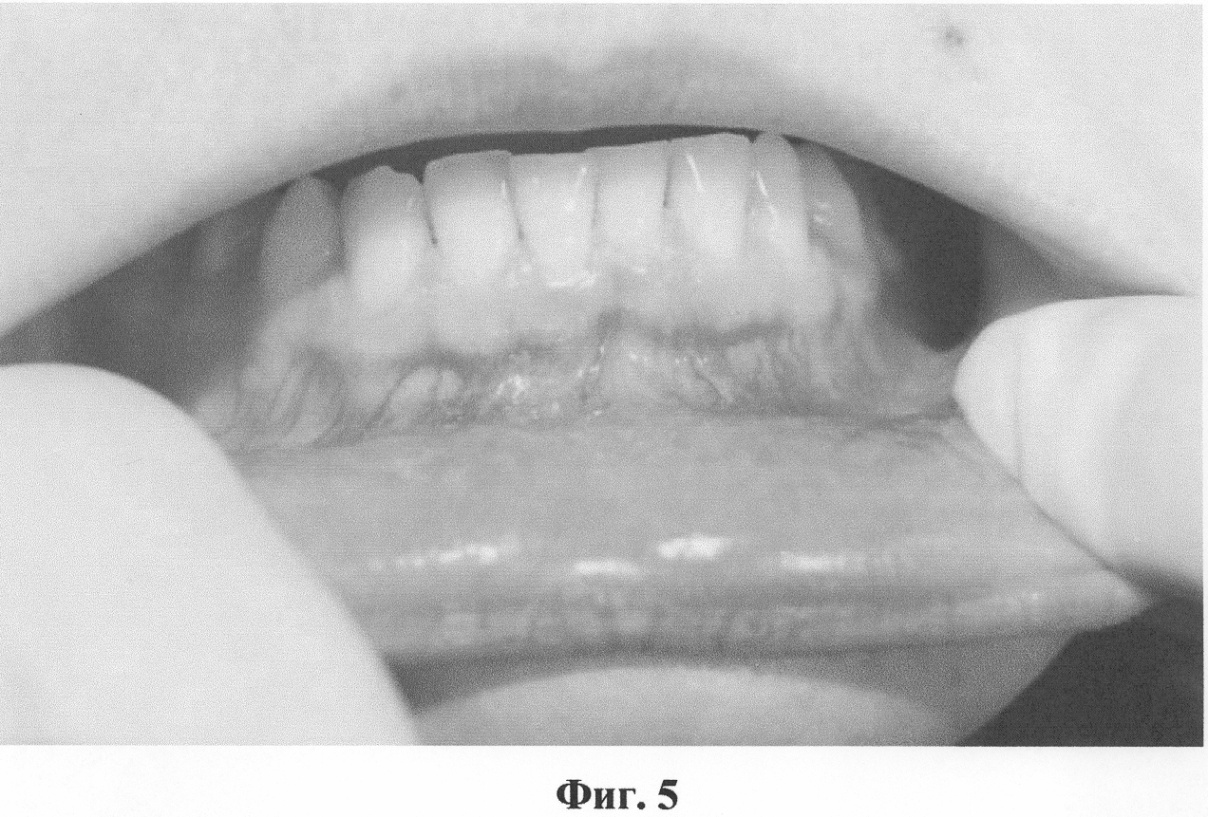

Фиг.5. Полость рта пациента с мелким преддверием до операции.

После курса противовоспалительной терапии проведена вестибулопластика на нижней челюсти по предлагаемому способу. На фото (фиг.5) показана полость рта пациентки с мелким преддверием до операции. Под инфильтрационной анестезией сделаны разрезы слизистой оболочки преддверия полости рта в вдоль уздечки нижней губы и слизистых тяжей на всю их длину между 33 и 34, 43 и 44 зубами. Тупо отслоены подслизистые ткани вдоль надкостницы на запланированную глубину преддверия, определено отсутствие тяжей и мышечных волокон (фиг.6). Мобилизованная слизистая оболочка подшита к надкостнице на глубине 12 мм резорбируемым шовным материалом (Dexon), вертикальные разрезы ушиты также с фиксацией к надкостнице на необходимой глубине (фиг.7).